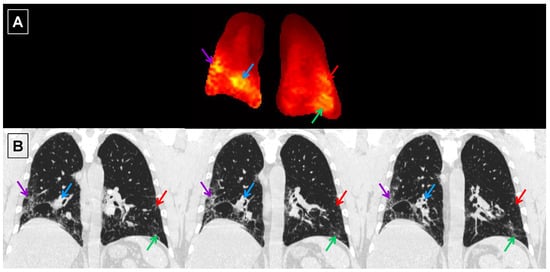

3.4. Subject Characterization with PFTs and HRCT